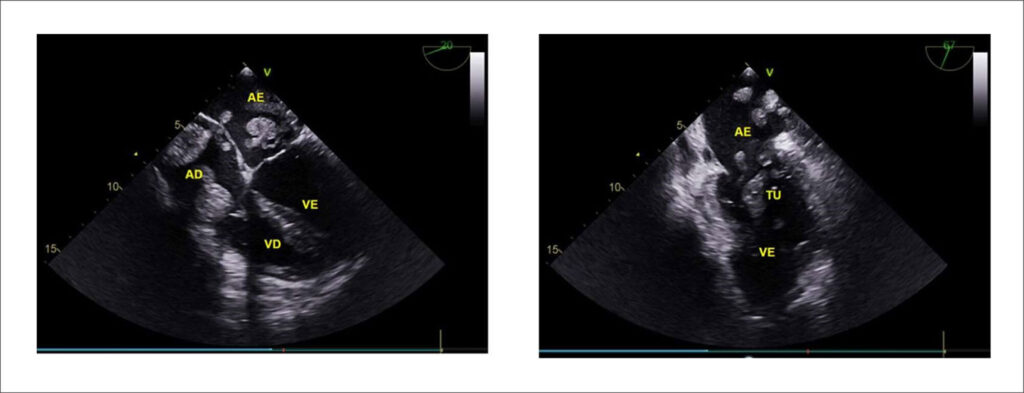

Cardiac Metastasis and Krukenberg Tumor: A Case Report

Primary cardiac tumors are rare, affecting between 0.0017% and 0.28% of the population. Secondary or metastatic tumors, on the other hand, are 40 to 100 times more frequent than primary tumors. The primary sites that most often metastasize to the heart are the lungs, breast, malignant melanoma, and hematological tumors. Cardiac metastasis secondary to ovarian tumors is infrequent and, in the cases described, mainly affects the pericardium, with no intracavitary lesions described. Metastatic neoplasms can reach the heart by these routes: hematogenous, direct extension, lymphatic vessels, and through the pulmonary veins and vena cava.,